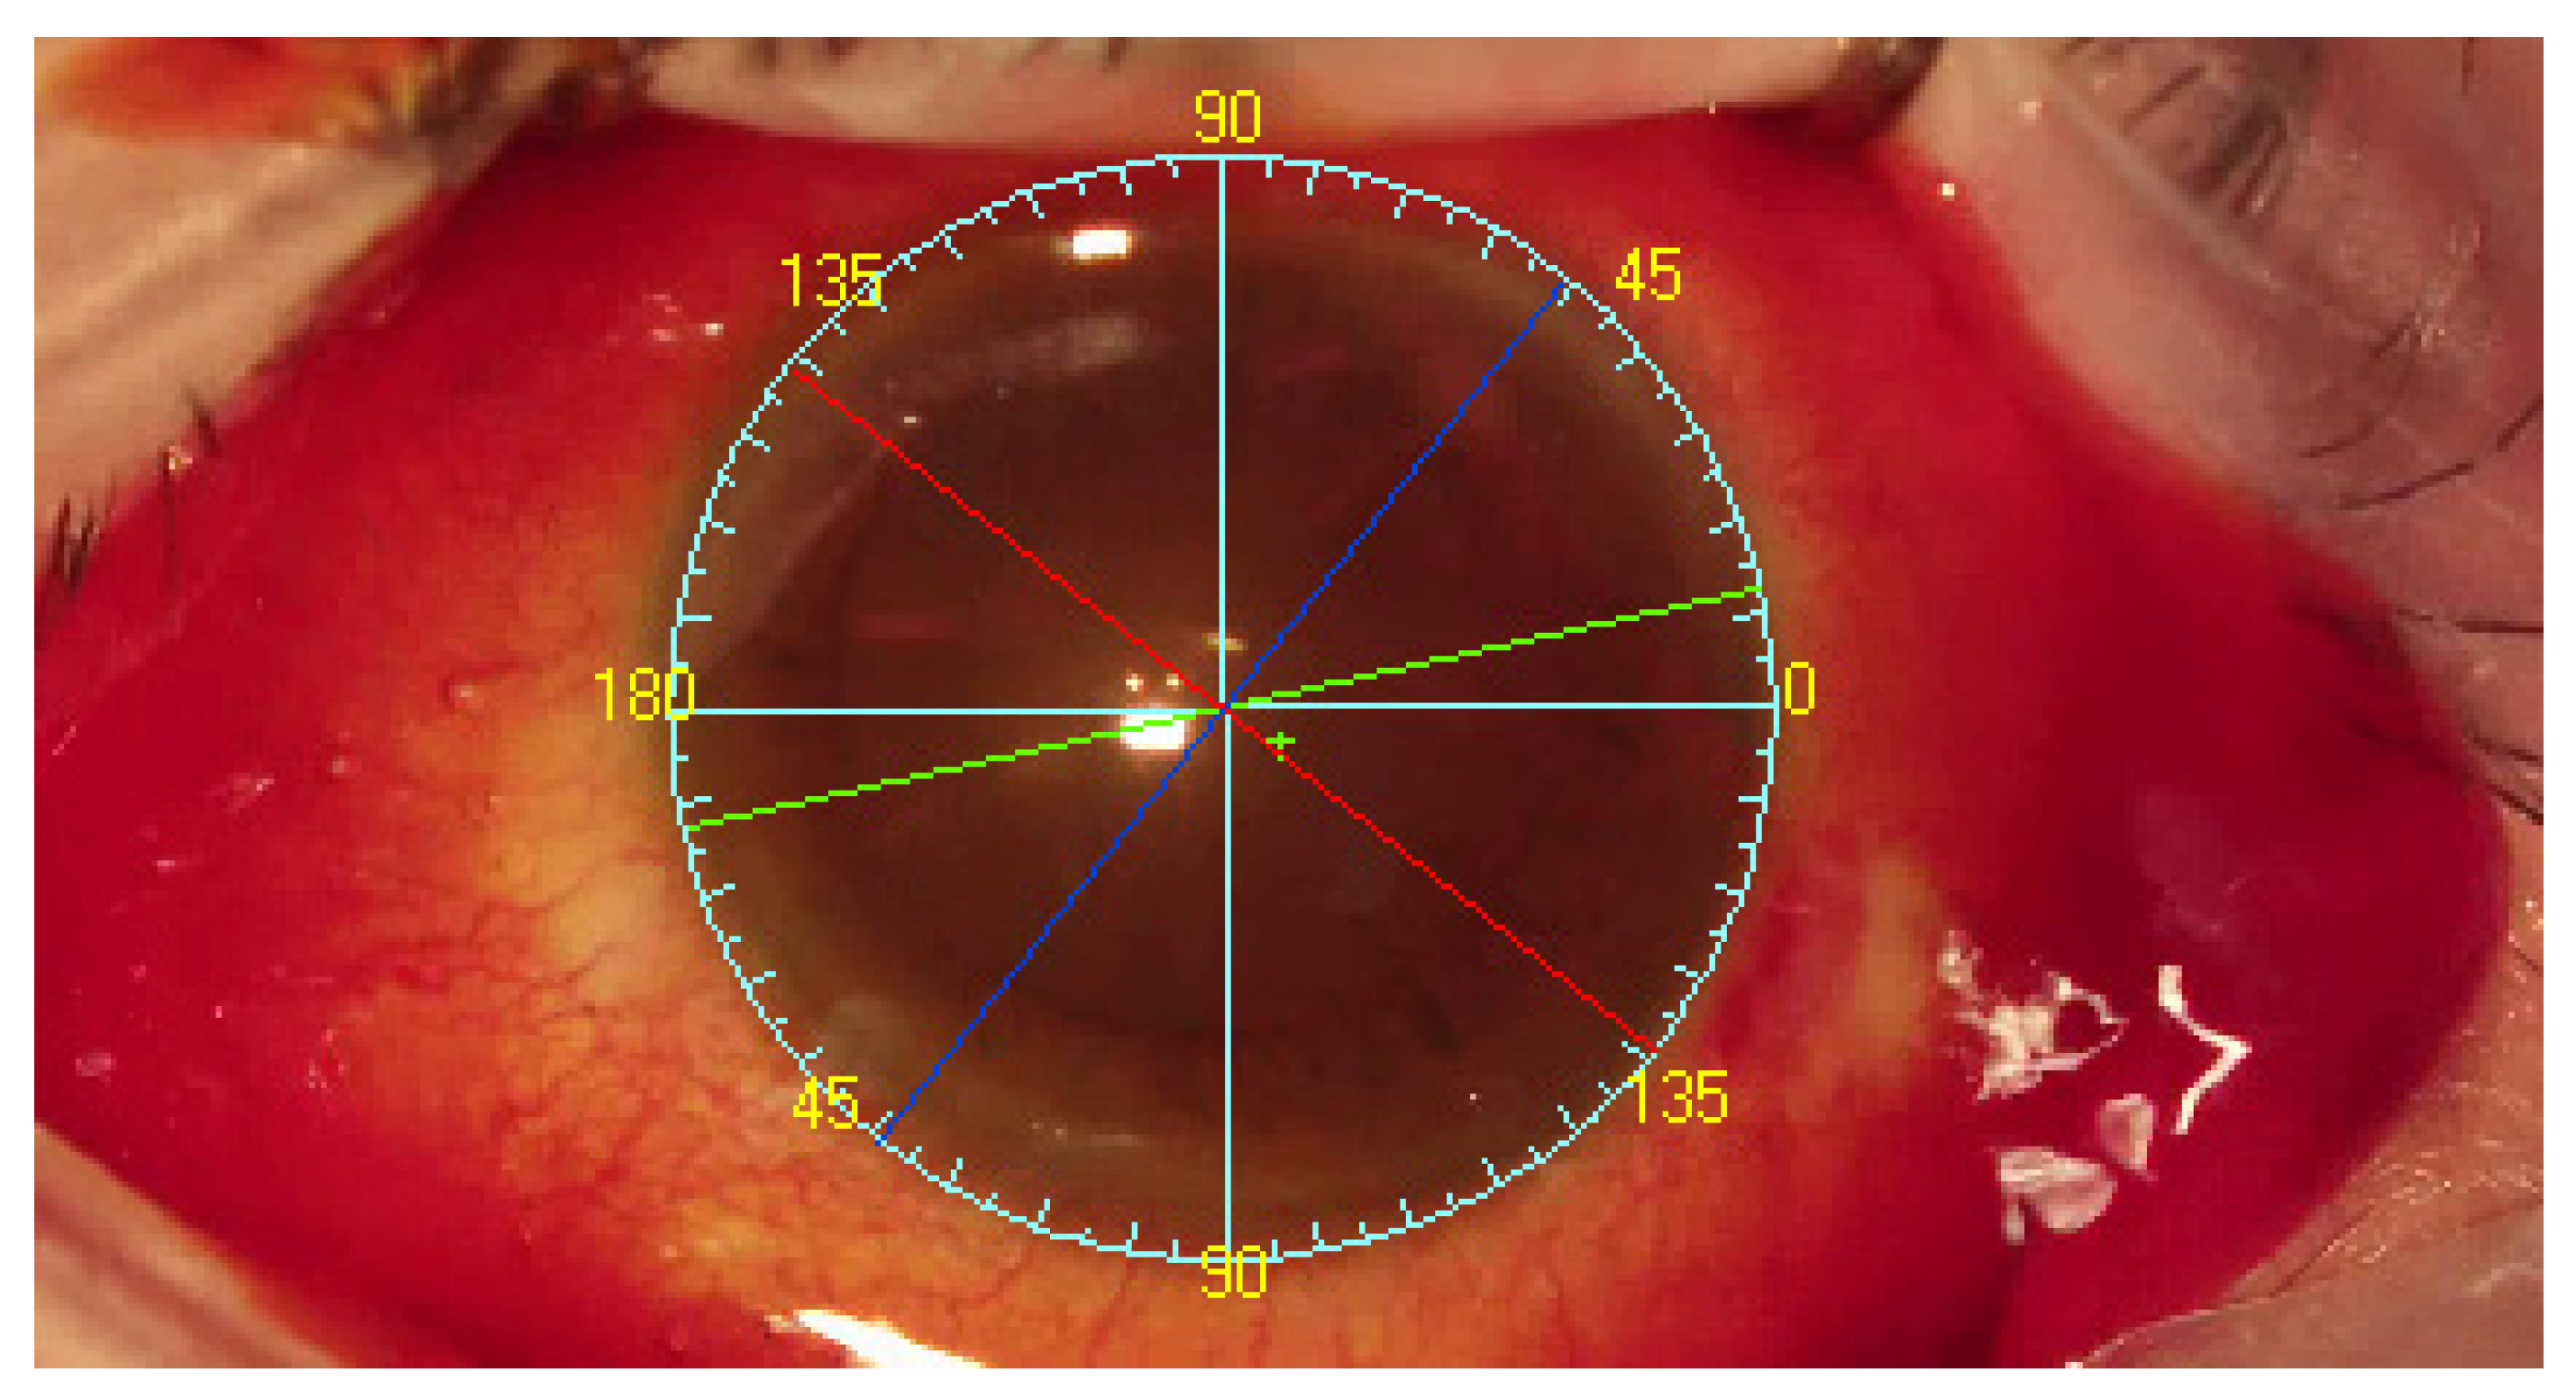

The INTEGRA system is based on an algorithm introduced by D. Lowe, the Scale Invariant Feature Transform [11]. The system tracks scleral vessels in the region of interest and detailed image analyses were previously described [3,7]. Notably, the system allows tracking of the vessels and superimposes the image regardless of the eyeball position, including cyclotorsia, in real time. The graphs representing the TABO scale, the flat and steep corneal meridians and the implant axis, as well as the location of the main incision, side-port incisions and the visual axis, are superimposed on the image from the operating microscope [3,7]. The INTEGRA is an open structure system. To work, it requires an image from any operating microscope and a reference image—a photo of the anterior segment of the eye and corneal topography. The central unit (computer) along with dedicated software processes the images. Reference images as well as planned intraocular lens axis and other parameters, e.g., visual axis, are introduced from the corneal topography. A schematic diagram of the operation of the system is shown in Figure 3.

Following completion of corneal topography with an Oculus Keratograph III (Oculus, Wetzlar, Germany) and anterior segment photography, the system could recognize tens of thousands of reference points on the sclera and determine the visual axis. The TABO scale is centered on the pupillary center comparing to reference image of scleral vessels in the region of interest. Visual axis coordinates were exported as the center of Placido rings from the topography. The visual axis is presented by the system to the surgeon. As the final step, the TABO scale was applied to the image (Figure 4) [3].

Figure 4. The INTEGRA system operation view: Blue lines and yellow numbers—TABO scale. Green cross—visual axis. Green arrows indicates the visual axis (not INTEGRA view), Dark blue line—flat meridian. Red line—steep meridian. Yellow line—main incision suggestion. Green line—intraocular lens implantation axis.